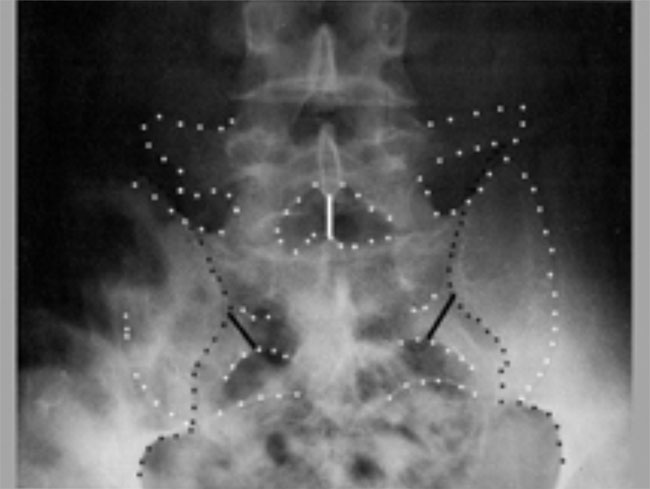

Roentgenograms taken before (Above) and after (Below) correction

of SIJD reveal a dysfunction of

the innominate bone cephalad and laterally on the sacrum. Note movement

of the PSISs relative to

the sacral foramina.